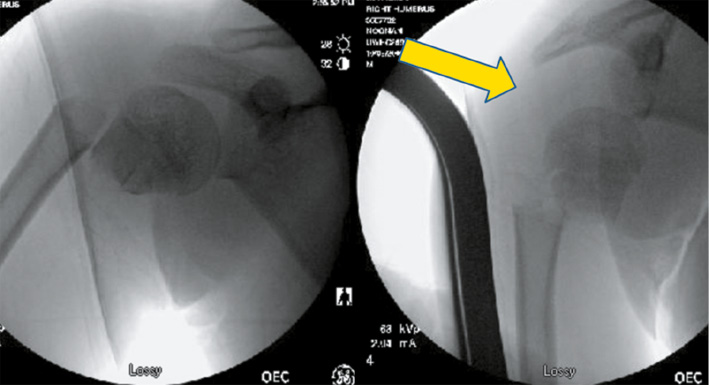

As mentioned above, one of the challenges is the difficulty in obtaining a reduction because it is very difficult to control the proximal fragment (Figure 5).

Figure 5. Attempts were made to gain fracture apposition with longitudinal traction in this 14-year-old boy, leading to inferior humeral head displacement.

jposna2023703_fig5.jpg